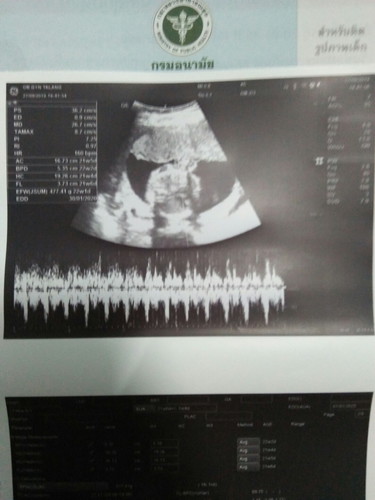

วันนี้ไปซาวด์คุณหมอบอกชาย100%จ้าา 22w1d ??